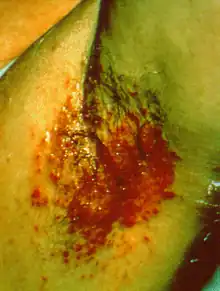

Streptococcal intertrigo is a skin condition that is secondary to a streptococcal bacterial infection. It is often seen in infants and young children and can be characterized by a fiery-red color of the skin, foul odor with an absence of satellite lesions,[1] and skin softening (due to moisture) in the neck, armpits or folds of the groin.[2]: 262 Newborn children and infants commonly develop intertrigo because of physical features such as deep skin folds, short neck, and flexed posture.[3] Prompt diagnosis by a medical professional and treatment with topical and/or oral antibiotics can effectively relieve symptoms.[4]

Streptococcal intertrigo commonly presents with a beefy-red, smooth, shiny lesion that has well-defined borders. There are no satellite lesions surrounding the area, and a distinct foul smell is common. The infection may be accompanied by general malaise and a low-grade fever. The folds of the neck are most commonly affected, but other areas with skin folds are also susceptible, including the armpits, groin, and anus.[9]

Streptococcal intertrigo is diagnosed by a medical professional after performing a detailed physical examination and taking an overnight culture of the affected areas. A second sample is tested with a rapid antigen detection test for Group A streptococcus.[18] Upon physical examination, streptococcal intertrigo commonly presents with a marked area of redness of the skin, a distinct, foul smell, and a lack of satellite lesions. The presence of satellite lesions, or lesions smaller and further away from the main affected region, may point to a differential diagnosis of candidal intertrigo, which is a more common cause of these characteristics. Streptococcal intertrigo is frequently underdiagnosed and should be considered as a causative agent when standard therapy for candidal intertrigo fails.[1]

A 2-year old female presented with a well-demarcated red, smooth plaque, foul smell, and no satellite lesions on the left armpit and neck for 2 weeks. They were initially treated for candidal intertrigo without improvement in their condition. The affected areas were swabbed, and the culture grew group A beta-hemolytic Streptococcus pyogenes that was sensitive to penicillin. They were then diagnosed with streptococcal intertrigo and prescribed amoxicillin plus clavulanic acid antibiotics for 7 days along with topical application of fusidic acid. The intertrigo completely resolved with this regimen.[9]